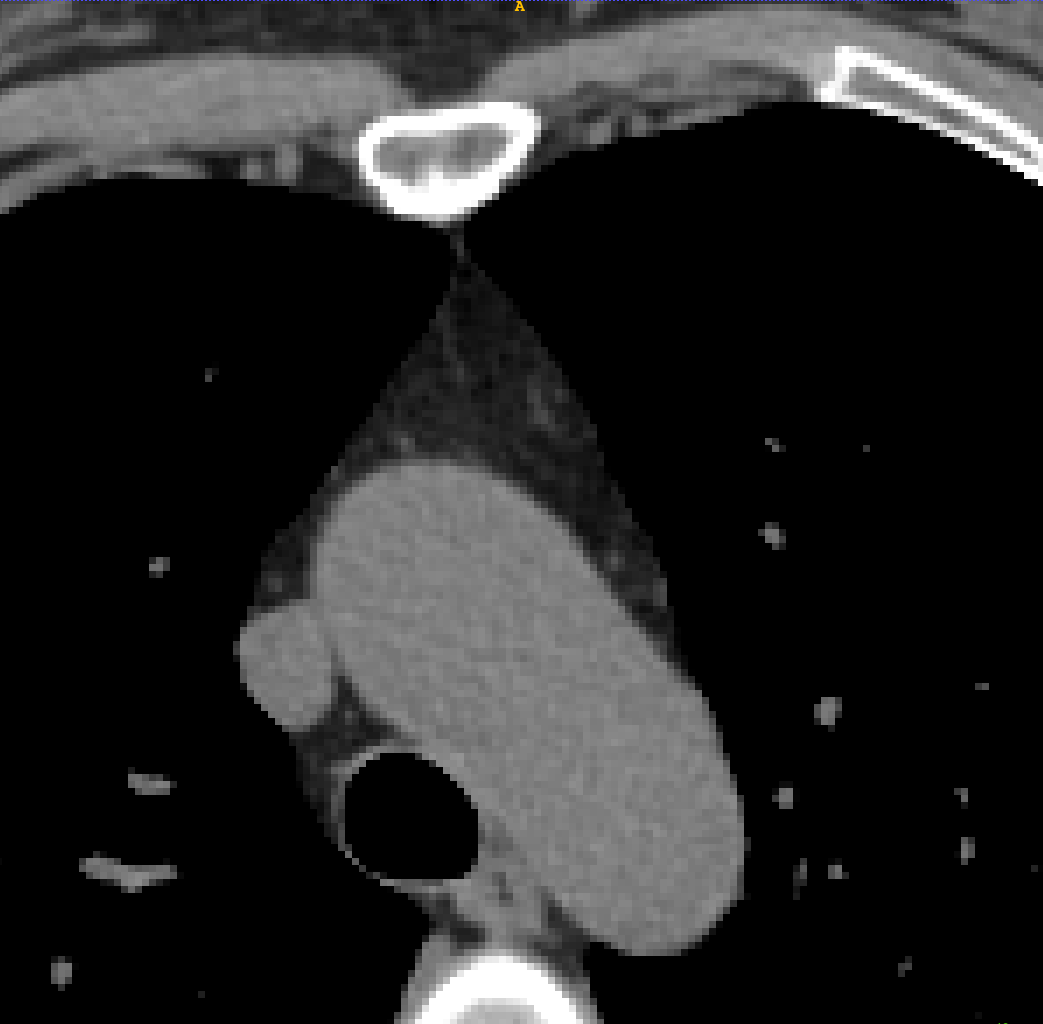

TABLE V: Visualization result on SegTHOR. Gray image registration result(row 1-2) shows the fitting ability of various methods. Mask image registration result(row 3-4) shows the regional continuity of various methods. The mask includes four parts: heart(green), aorta(yellow), trachea(blue) and esophagus(red).

[Uncaptioned image] [Uncaptioned image] [Uncaptioned image] [Uncaptioned image] [Uncaptioned image] [Uncaptioned image]

F M VoxelMorph Ants deedsBCV Ours

We selected four images of large deformations occurring at different locations from different CT, the visualization results are shown in Table V.

Rows 1-2 shows the CT gray image registration results. The task is to register MM to FF. From the visualization of gray image results, we can see that although ANTs and deedsBCV has high dice scores, the visualization results look unrealistic. Meanwhile, deep learning methods look smoother. The sixth column shows the results of our method. The fitting effect is improved compared to previous methods.

Rows 3-4 shows the mask registration results. The background of each image is FF. We could judge the performance by observing the fitting degree of the mask and background. In many practical tasks, we use a registration algorithm to register MM’mask to get the mask of FF. There may be a situation where the gray image fitting is good, but the mask result is poor. This may be because the continuity of the registration field is not good enough.